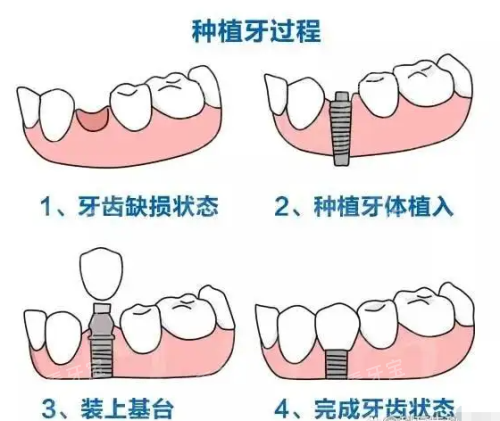

?小创口种植技术:创口仅3-4毫米,比拔牙伤口还小,当天就能吃饭

?即刻种植:当天拔牙当天种植,避免牙齿缺失的空窗期

?种植修复:联合省级医师开展即刻种植、全口种植修复,缩短治疗周期